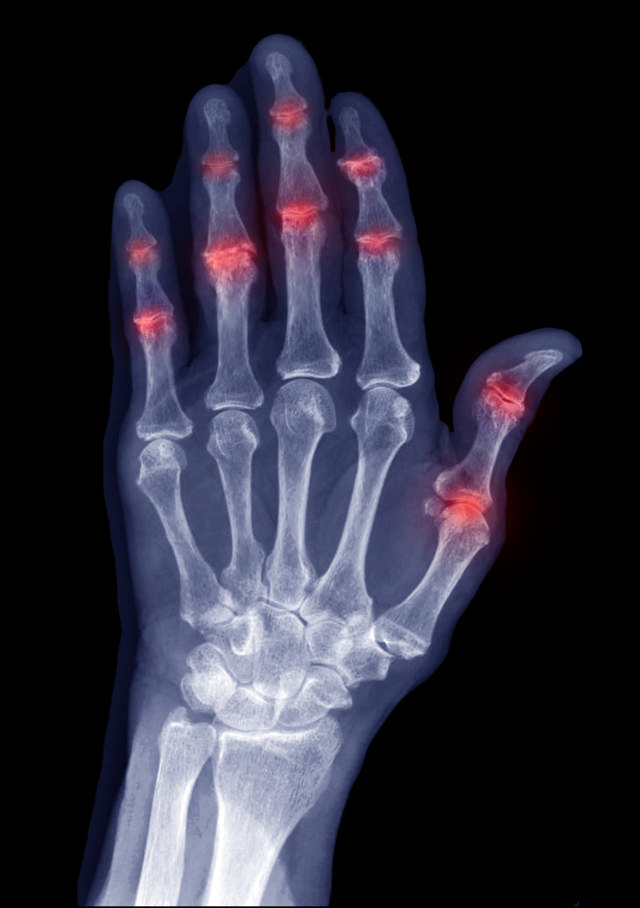

Sawiro: iStock

Dhabar xanuun- iyo kaarka laalaabatooyin faraha waa u caadi cudurka psoriasisartritt (iStock).